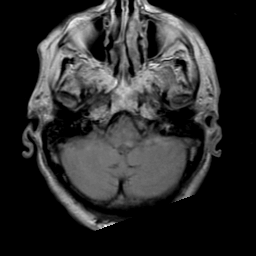

Meningioma, MR Study #2 -- Slice #2

[Home][Help][Clinical] Slice 2